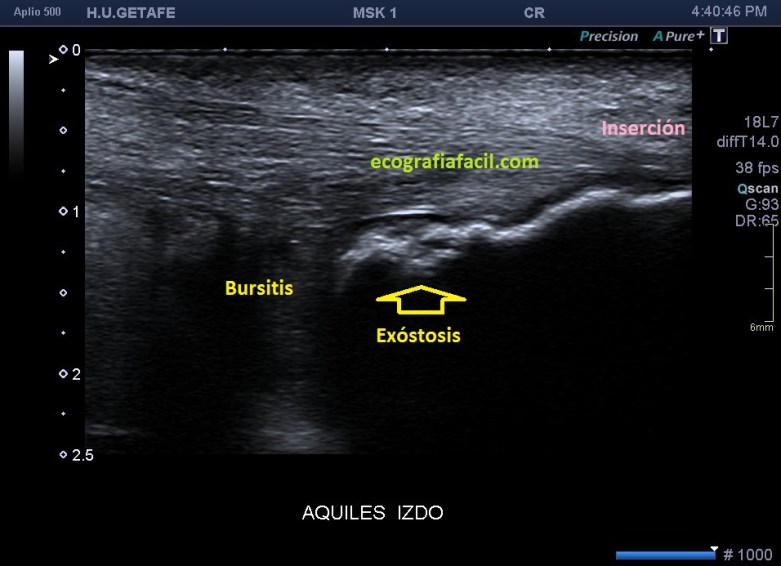

En el texto anterior hemos visto enmarañadamente muchos conceptos asociados a patologías que pueden darse en esta pequeña región del Aquiles. He nombrado el Síndrome de Haglund. Este es un síndrome que incluye tres aspectos, a nivel del aspecto posterior del calcáneo con una afectación de la bursa retroaquílea debido a la presencia de una exóstosis.

Si observamos la bursitis retroaquílea de la imagen 11(flechas amarillas), además la exóstosis de la imagen 13 y deformidad en la piel, observable sin ecografía podemos estar ante un síndrome de Haglund de esos de libro…y tendremos una imagen ecográfica como la de la imagen 14.

Como has visto en la imagen 1, la bursa retroaquílea no debe verse, ese receso debe tener como mucho una mínima cantidad de líquido, que como digo es normal, pero no lo que observamos en la imagen 11 donde vemos una imagen heterogénea ocupando esa región.

En la imagen 14, como no podía ser de otra manera, observamos todo y es por definición la típica imagen de S.Haglund.